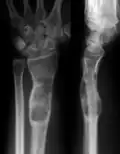

X-ray showing enchondromas localized in the lower part of the radius of a 37-year-old patient affected with Ollier disease -